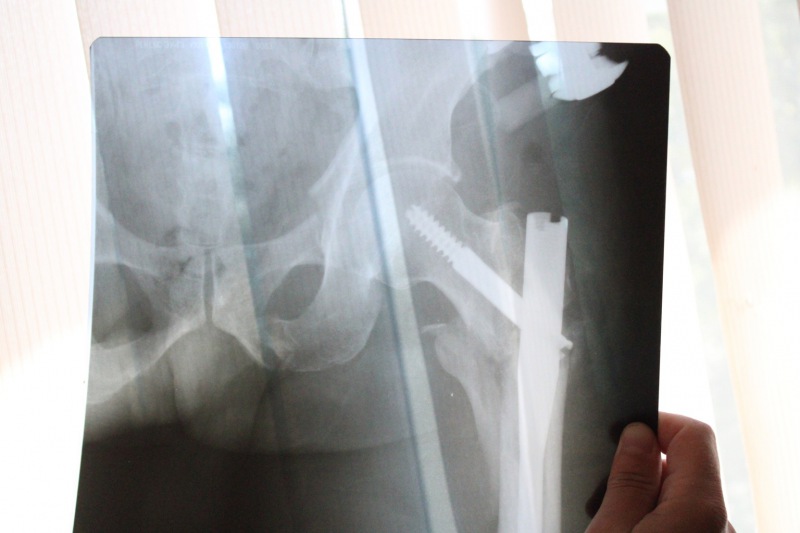

"Состояние пациента при поступлении было тяжелое: перелом левого бедра, перелом костей таза, перелом правой пяточной кости. У него присутствовал травматический шок 3-й степени, давление было 70/40", - рассказал травматолог-ортопед нейрохирургического отделения БСМП Сергей Казенов. По счастливой случайности остальные части тела, а также внутренние органы при падении не пострадали - звучит фантастически, но это факт!

Павел 3 дня провел в реанимации, где его состояние было стабилизировано. 11 июля мужчину прооперировали. Бригада медицинских работников под руководством заведующего нейрохирургическим отделением Леонида Овечкина несколько часов собирали воедино многочисленные отломки. "Мы применили остеосинтез гамма-стержнями. Благодаря этой современной методике поврежденные кости надежно фиксируется, что позволяет им быстрее срастаться. На кости таза также установлен аппаратом внешней фиксации", - объяснил Сергей Александрович.